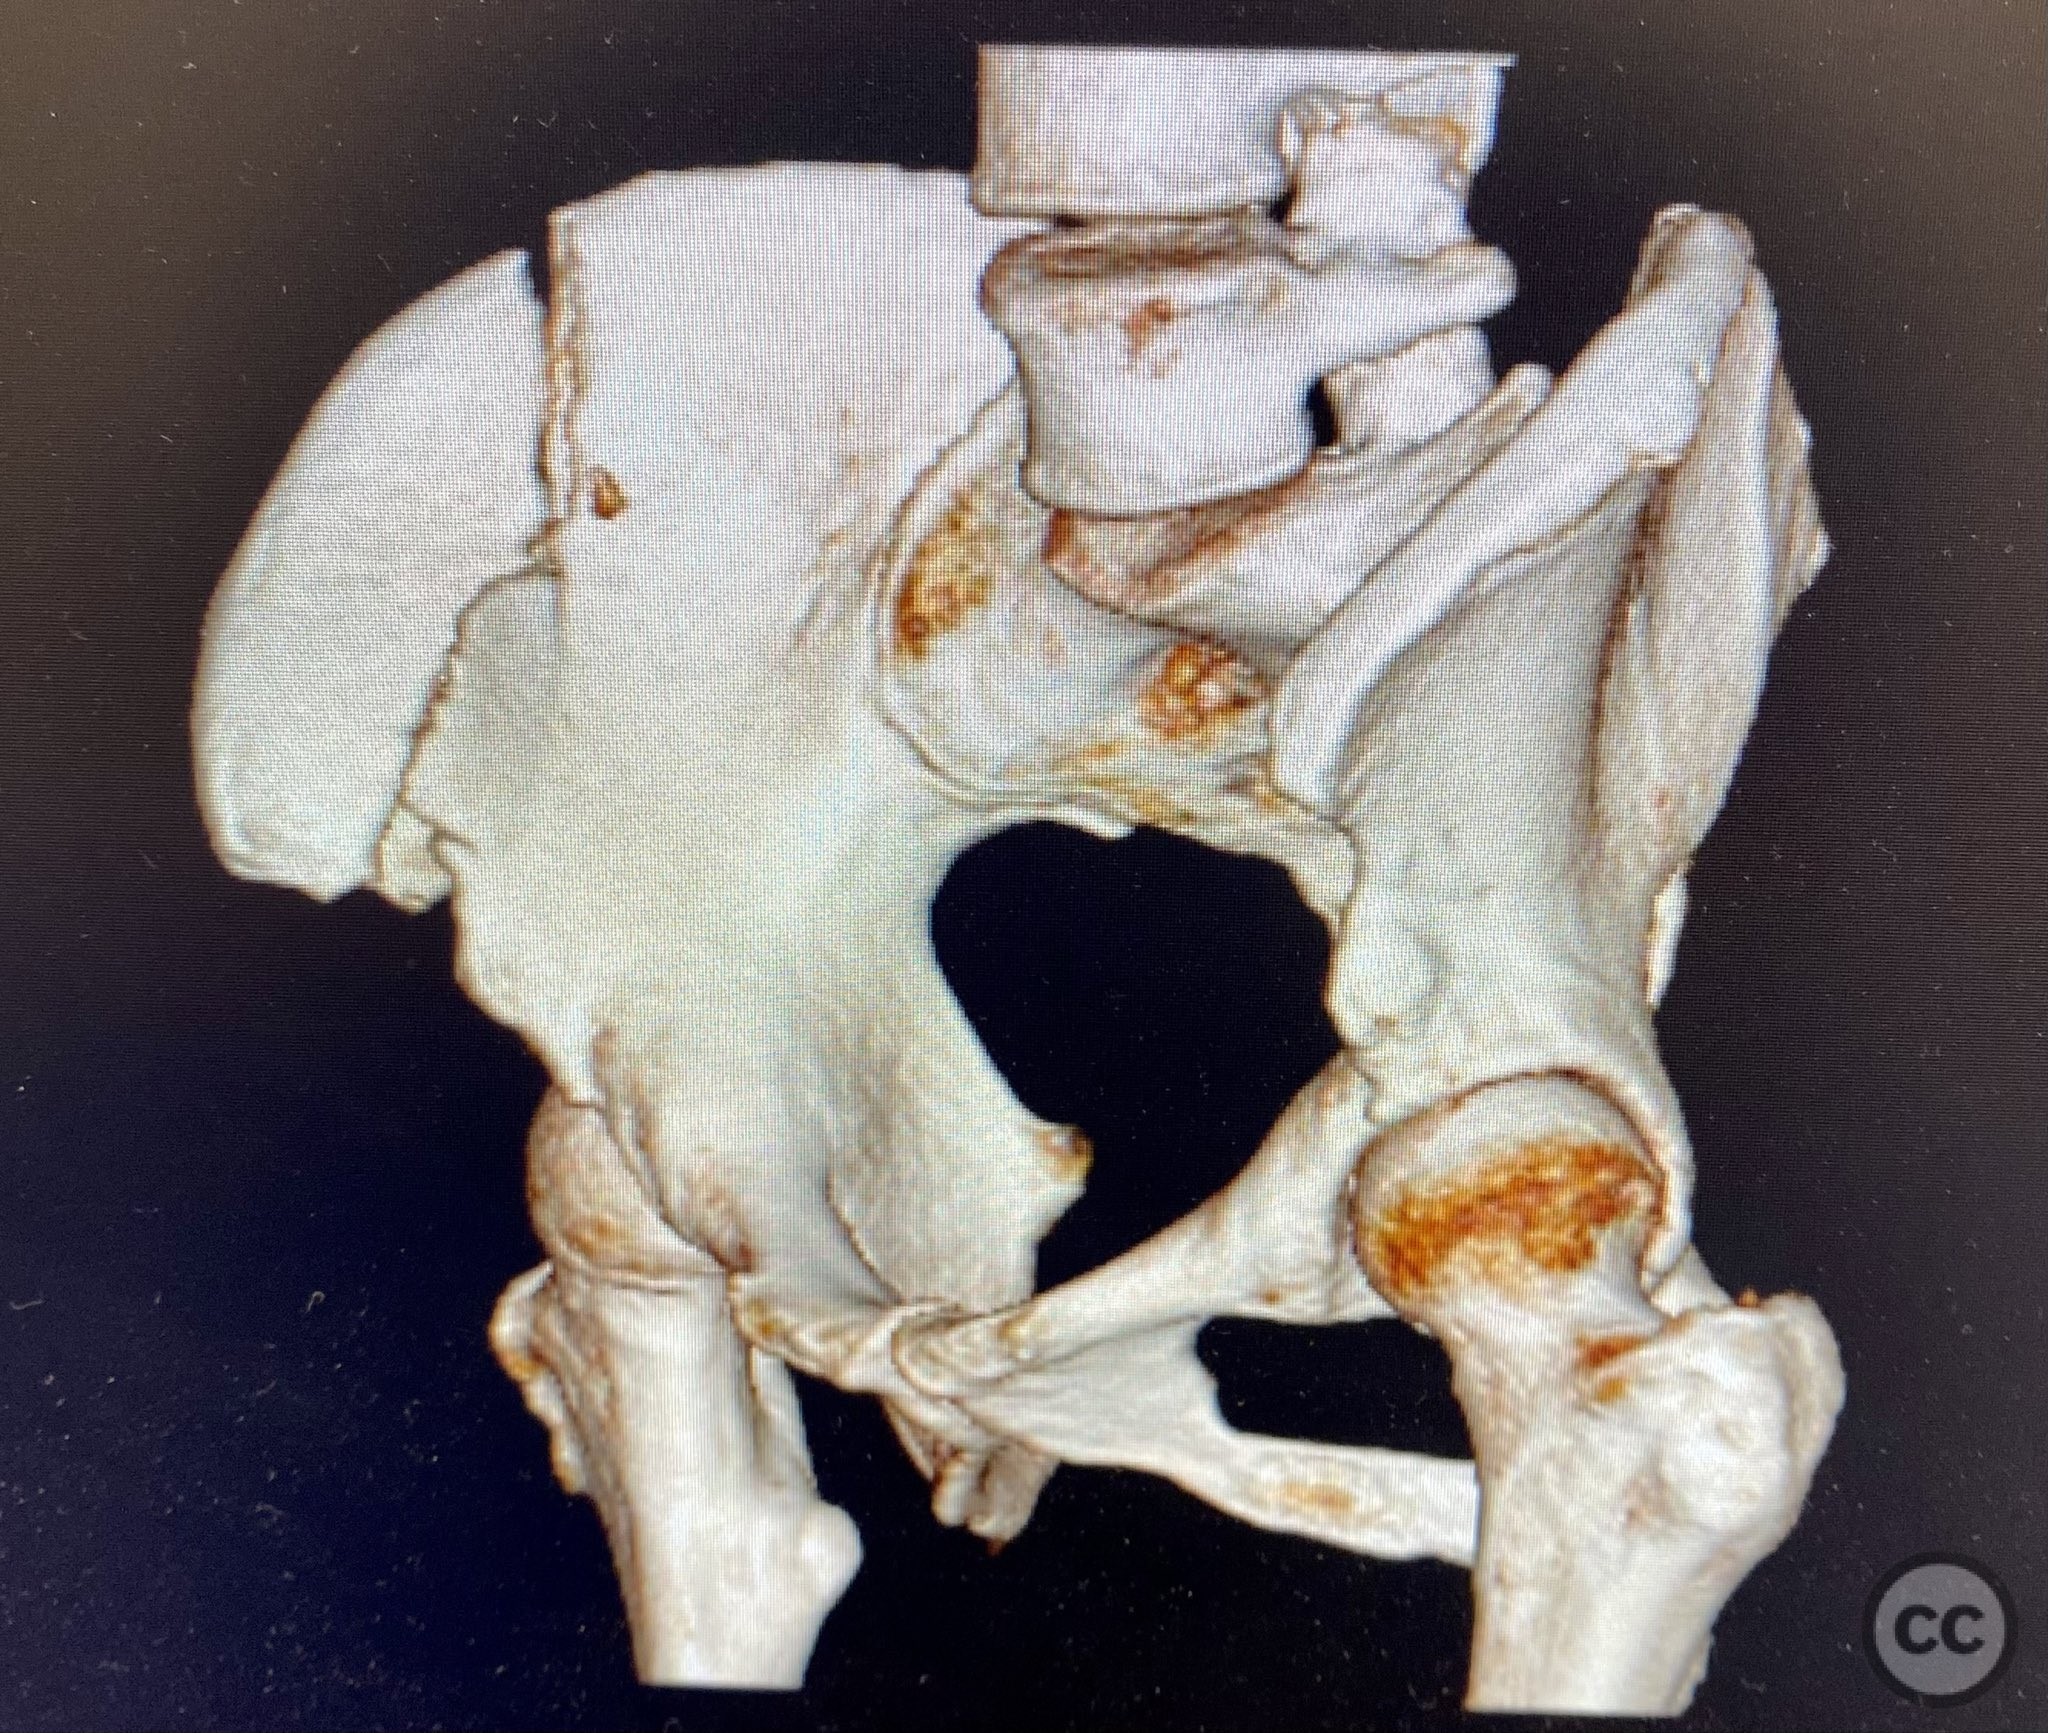

Clinical Details

Clinical and radiological findings:  A middle-aged patient sustained a closed, displaced, and comminuted fracture of the right os ilium following a fall from height. Initial AP pelvic radiograph and 3D surface rendered imaging demonstrated significant comminution, displacement, and poor bone quality. The patient was unable to mobilize due to pain. No associated neurovascular deficit or additional pelvic ring injury was reported. AO/OTA classification: 61B2.2 (partial articular, comminuted iliac wing fracture).